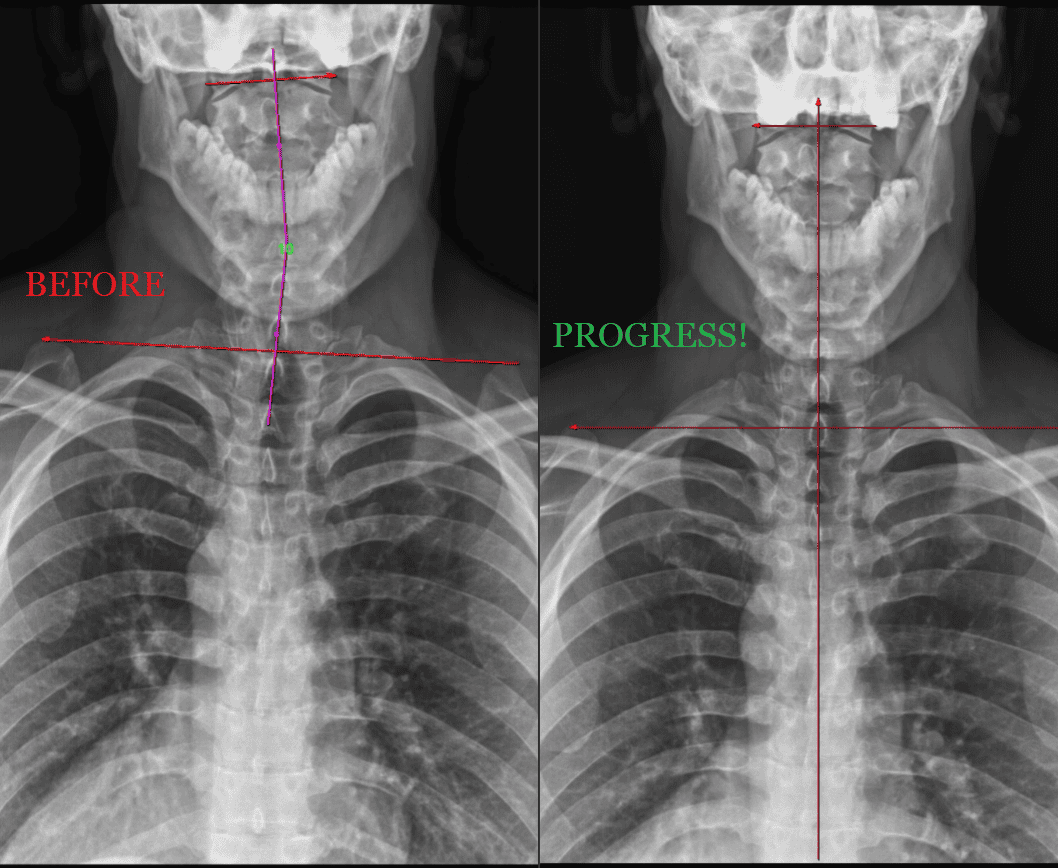

The Digital Posture X-Rays below are Before & After X-rays of practice members that got AMAZING RESULTS via our Corrective Care health program over the course of just 1 year!

By taking digital spine x-rays, chiropractors at Camarata Chiropractic can identify problems with the spine's alignment, detect bone density changes, and assess the degree of degeneration that may exist. This information helps chiropractors to identify underlying causes of spinal misalignment, such as injury or degeneration, and develop a treatment plan that addresses these issues. With the help of digital spine x-rays, chiropractors can also monitor the effectiveness of treatment over time, making any necessary adjustments to ensure that patients receive the best possible care.